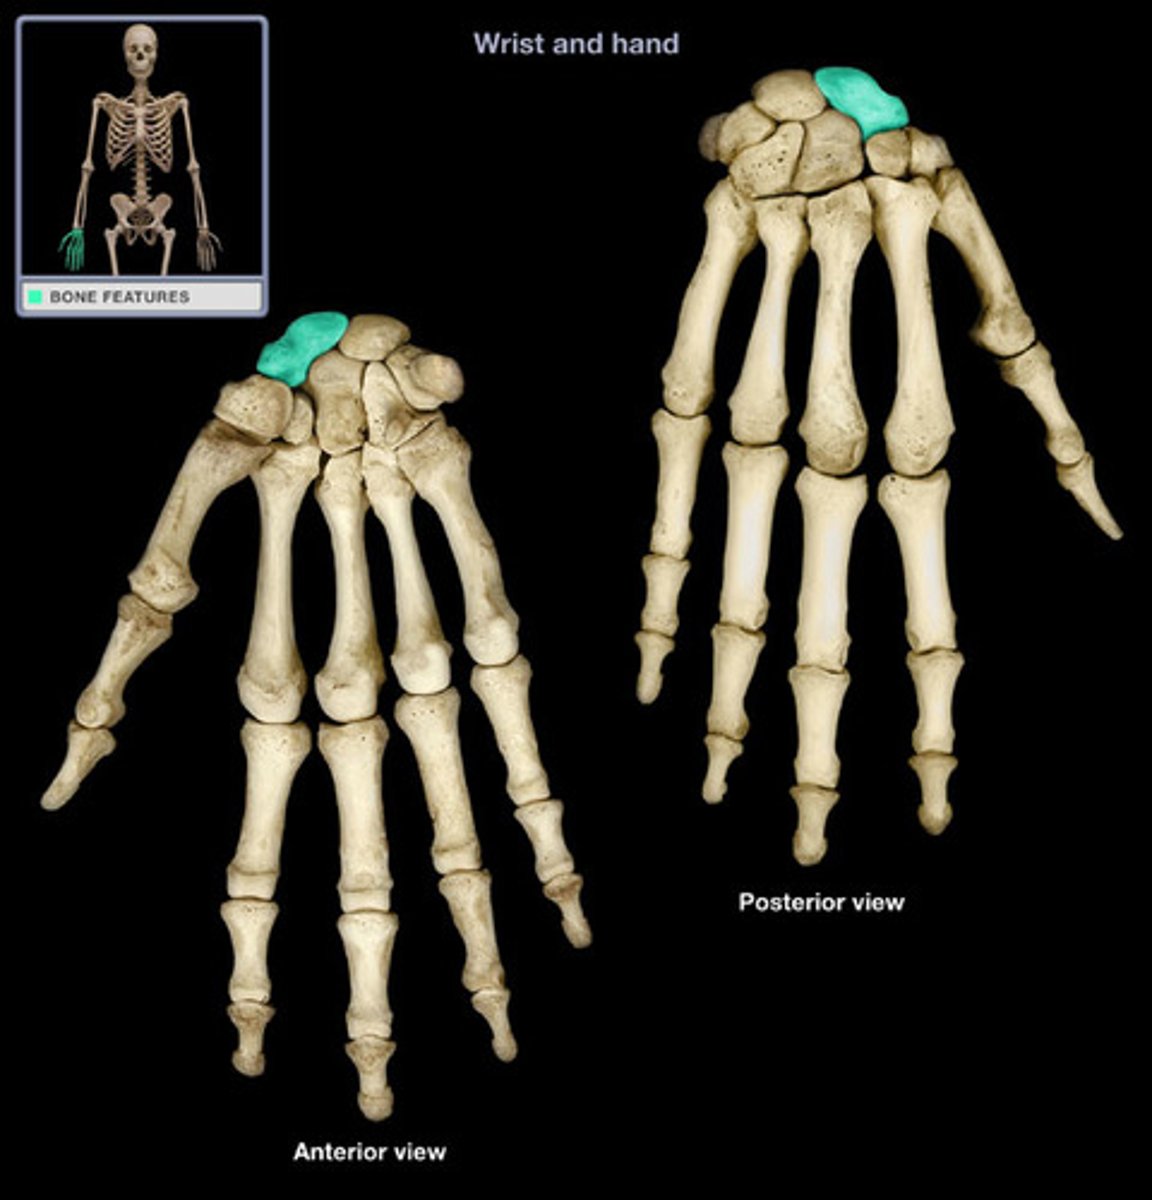

Characteristics of the wrist (or carpus):

- composed of 8 carpal bones arranged in proximal and distal rows of 4

- give flexibility to the wrest, each bone glide on the adjacent to it

- convex posteriorly and concave anteriorly (from side to side)

Proximal row of wrist bones (lateral to medial):

- scaphoid,

- lunate

- triquetrum

- pisiform

Scaphoid of the proximal row of the wrist:

- Largest bone in the proximal now

What does the scaphoid of the proximal row of the wrist articulate with?

Articulates with the radius

Lunate of the proximal row of the wrist:

Moon shaped